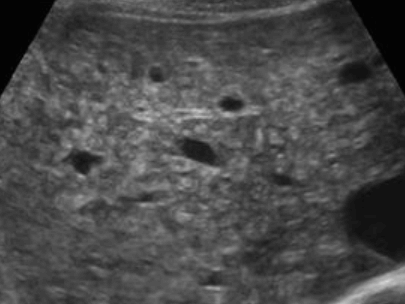

US finding

- 전반적으로 에코가 거칠게 보이는 간경변의 초음파소견과 비슷하여 주의가 필요함.

- 크기가 비슷한 고에코 또는 저에코 병변들이 보인다.

- 다중반사에 의한 comet-tail artifact를 보인다.